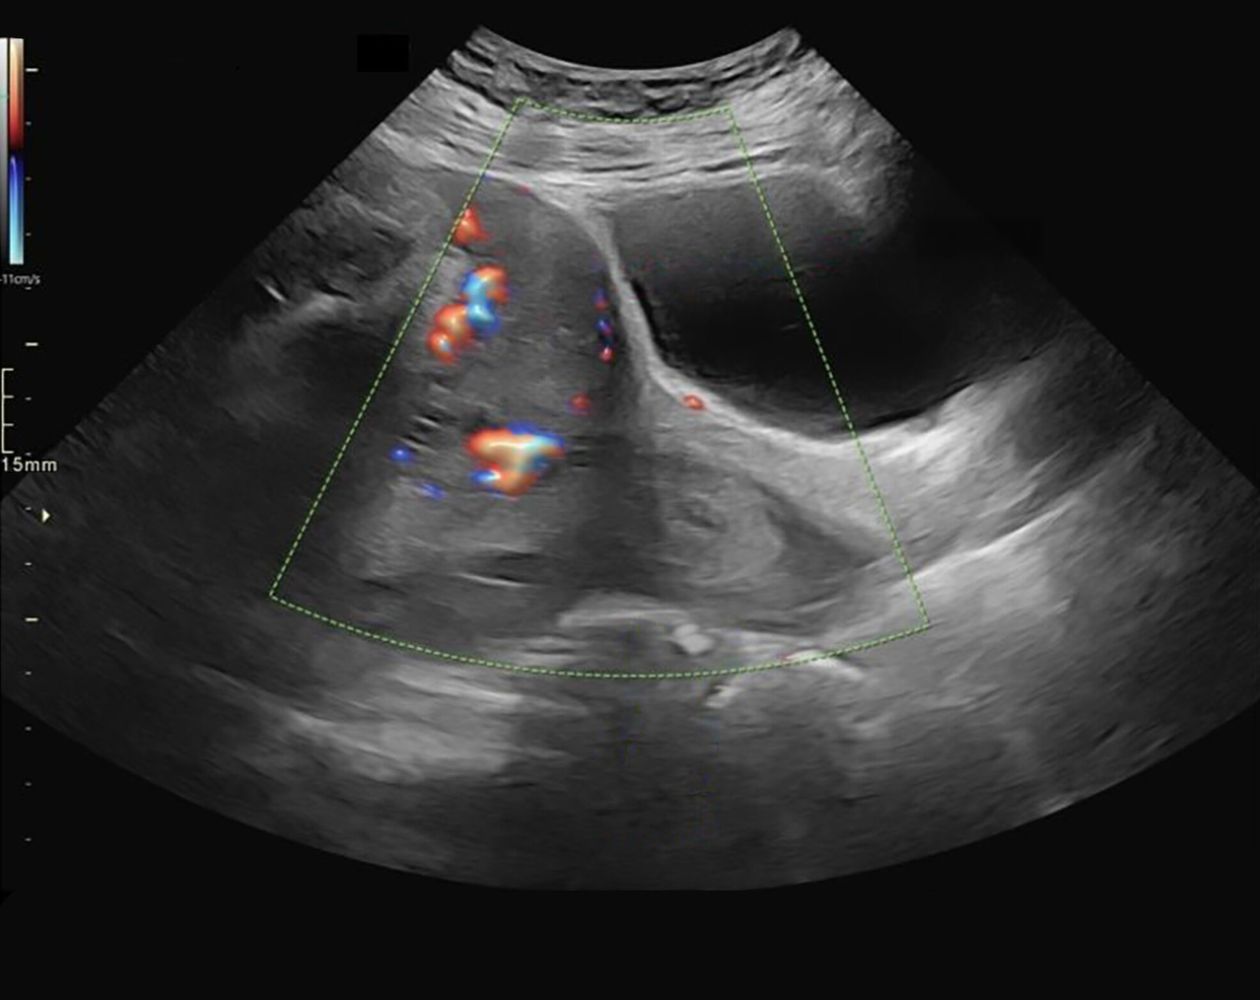

• Transabdominal or transvaginal ultrasound with color Doppler shows fetal vessels overlying the internal os and decreased blood flow within fetal vessels.